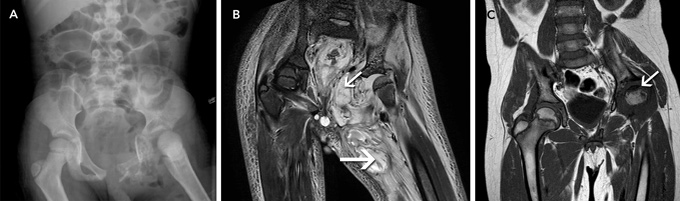

In our patient, plain radiographs (which are usually normal for the first 7–10 days8) and magnetic resonance imaging (MRI) scans showed extensive bony and soft tissue destruction of the left hemipelvis, hip and thigh. Is it plausible that these changes occurred within 2 weeks, considering the patient’s history? As we were unable to find supporting reports in the literature, this matter was discussed within various hospital departments. Concerns were raised that the time frame was too short to cause this level of destruction. It was proposed that the mixed flora that were cultured could cause a high level of destruction within 14 days. Although plausible, there was no direct evidence to support this theory.

When during the course of the infection did the bowel perforation occur? In the literature, we found two case reports of a bowel perforation associated with pelvic osteomyelitis. Both occurred in adult patients, and bony infection was secondary to Crohn disease in both cases.9,10 On arrival at our hospital, our patient’s radiographs showed dilated loops of bowel and no signs of free gas. The MRI scan showed oedema and signs of inflammation of the soft tissue at the perineum, surrounding the rectum, urethra, bladder and sigmoid colon. Free fluid was seen within the pelvis; however, there was no obvious pelvic collection. Enteric flora were cultured from the initial intra-operative swabs. These factors indicate that the bowel perforation was probably present on arrival, possibly as a sealed perforation, which was only detected 5 days after the initial debridement. Although we were unable to ascertain the cause of the bowel perforation, we believe that its association with pelvic osteomyelitis was significant.